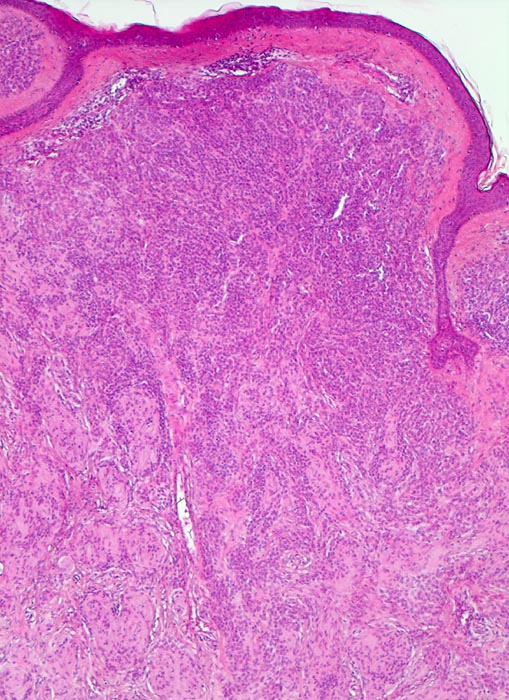

dermaler Naevuszellnaevus

benigner Tumor

Haut, Rumpf

Haut

Unauffällige Epidermis. Zwischen den Naevuszellen und der Epidermis schmale Schicht von zellarmem Bindegewebe. Ein dichtes Infiltrat von Naevuszellen füllt das Corium aus. Zwischen den Naevuszellen vereinzelte Spaltbildungen (typischer Fixationsartefakt).

Graubraune, leicht erhabene, scharf begrenzte Hautveränderung über dem Schulterblatt.

Histologie

50